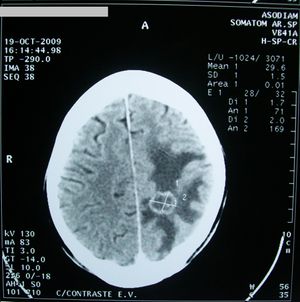

الشكل (2) صورة مرنان مغنطيسي للدماغ تظهر وجود ورم انتقالي دماغي (الكتلة البيضاء) وحولها تظهر منطقة الوذمة الدماغية (ناقصة الإشارة أو «سوداء»).

ويعتمد في المرحلة الثانية من التشخيص عادة على تصوير الدماغ (بالرنين المغنطيسي أو التصوير الطبقي المحوري).

إن الوذمة في (الشكل 2) موضعة في منطقة محدودة من الدماغ حول الكتلة الورمية، أما في حال كون الوذمة الدماغية معممة فعندها تُظهر الصور الدماغية إمحاء في الأثلام وأحياناً صِغراً في حجم البطينات الدماغية نتيجة انتباج النسيج الدماغي.